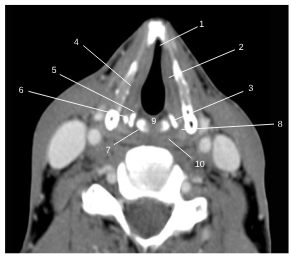

Fig. 62.7 Étage glottique : TDM, coupe transversale.

1. Commissure antérieure de la glotte. 2. Pli vocal. 3. Cartilage aryténoïde. 4. Espace graisseux paraglottique. 5. Processus vocal du cartilage arétynoïde. 6. Processus musculaire du cartilage aryténoïde. 7. Cartilage cricoïde. 8. Espace inter-thyro-aryténoïdien. 9. Commissure postérieure de la glotte. 10. Pharyngolarynx.